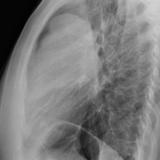

Case 8b Thymoma Lat

Date: 03/27/2009

Views: 14096